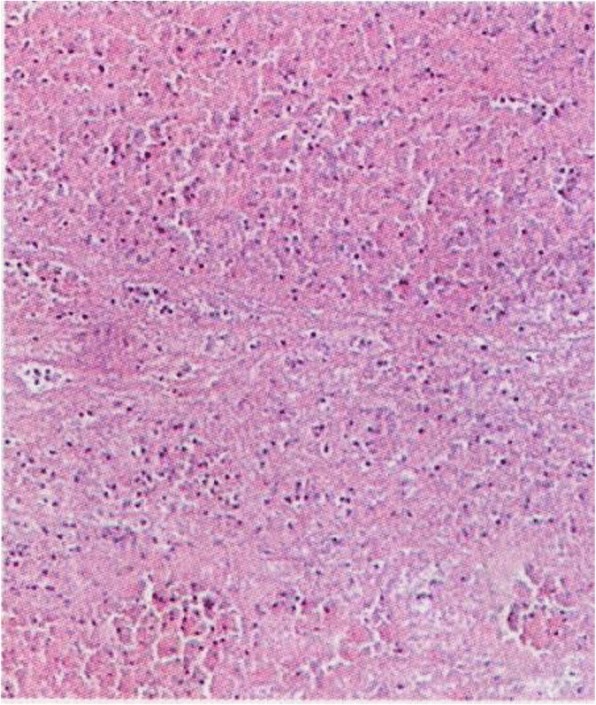

A high-density image of the middle CBD with a markedly dilated biliary tree was revealed on the second CT (Fig. 3). Thus, ERCP was repeated. A long filling defect was noted in the dilated common bile duct (Fig. 4), and a blood clot (maximum diameter 35 mm × 10 mm) was extracted with a basket (Fig. 5). Then, an endoscopic nasobiliary drainage (ENBD) tube was inserted into the CBD to ensure continued biliary drainage. Two days later, her temperature returned to normal, and abdominal pain was relieved. Histopathological examination revealed massive red blood cells with white blood cells and tissue necrosis (Fig. 6). After the treatment, she recovered and was discharged without any other complication.